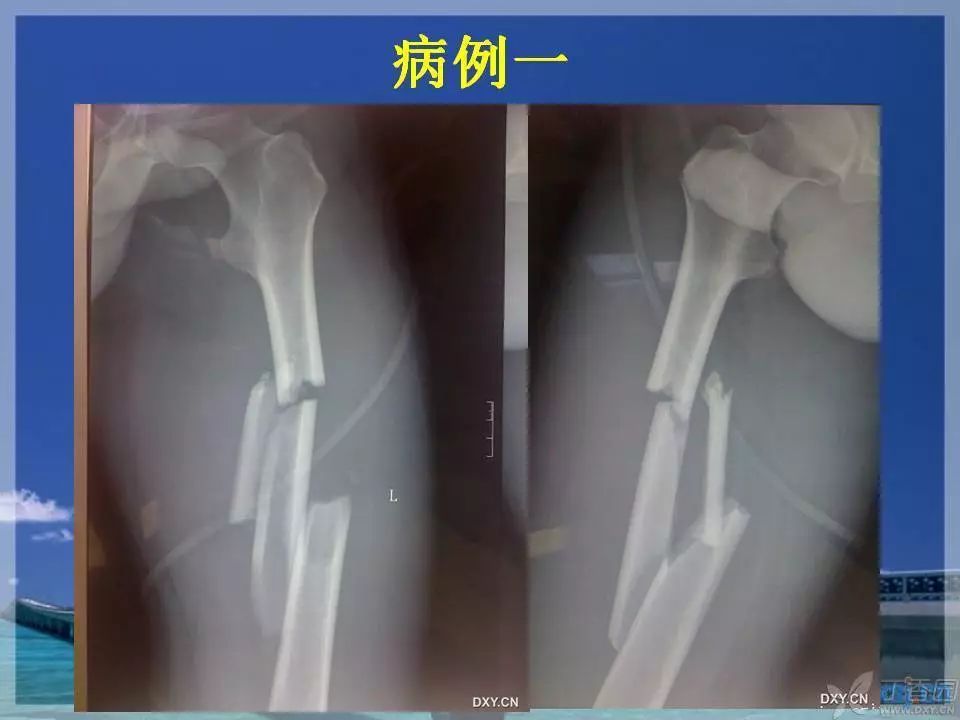

股骨干骨折是临床常见骨折之一,闭合复位髓内针固定治疗已成为首选。那么复位标准是怎样的?骨折块分离多少可以接受?钢丝可不可以用?不扩髓可以吗?相信看完下面这个课件你会有所收获~

1. ppt 中提到蝶形骨块移位大于 1cm 会影响股骨干骨折的愈合,这是一个台湾学者的观点,图中可以看见股骨内侧和后侧已经有骨痂生长,所以说 1cm 这个数据有待商榷。大于 1cm 的移位骨折愈合也不是什么问题。